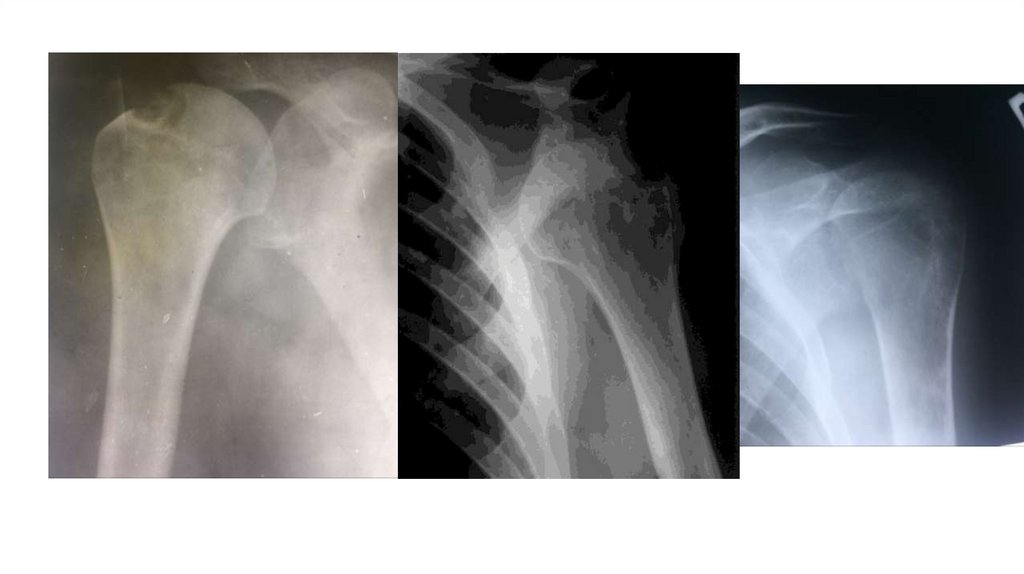

Воспалительные заболевания опорнодвигательного аппарата

заболевания опорнодвигательного аппарата»